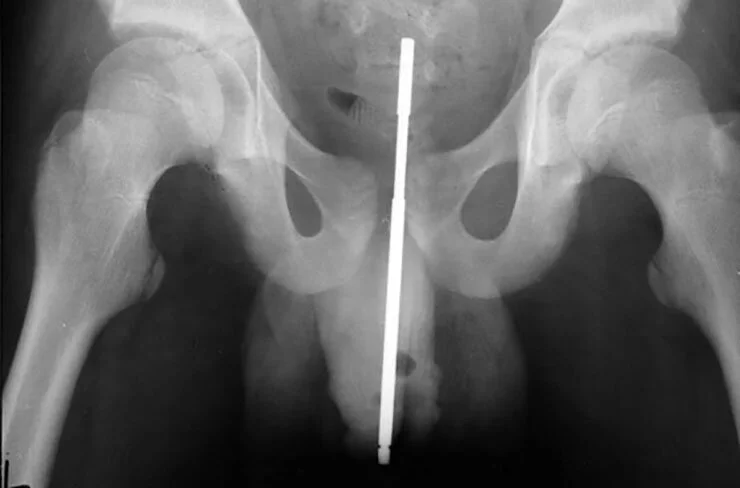

PENIS

• COCK PLUG

• TONGUE RING

• BALLOON

• STRING OF MAGNETIC BEADS

• “PLAYING WITH PHONE AND FELL ASLEEP WHEN HE WOKE UP HIS STYLUS WAS IN HIS URETHA. INJURY OCCURRED 4 DAYS AGO AND DIDN’T SEEK TREATMENT”

• PEN

• PENCIL

• PAINTBRUSH

• “METAL SCREW IN HIS URETHRA TO CAUSE AN ERECTION”

• WIRE HANGER

• LANYARD

• “HAS HAD A MARBLE IN HIS PENIS FOR THE PAST 4 YEARS AND DECIDED HE NEEDS IT REMOVED”

• GLUE